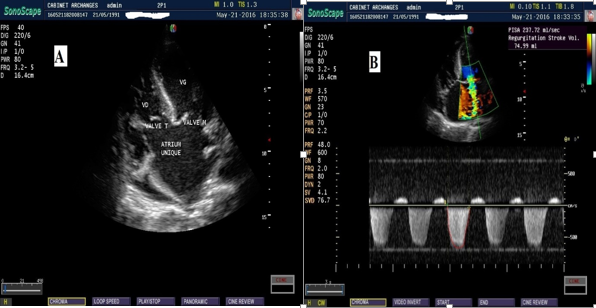

L’échographie doppler cardiaque a fait le diagnostic d’une oreillette unique desservant les 2 ventricules avec maintien d’une bonne concordance ventriculo-artérielle. Les valves mitrales et tricuspidiennes étaient déformées courtes donnant une fuite tricuspidienne moyenne et une fuite mitrale importante ; il n’y avait pas de fente mitrale ni de shunt gauche droite aux niveaux ventriculaire et artériel. Il n’y avait pas d’anomalie du retour veineux pulmonaire ni de persistance de la veine cave supérieure gauche. La fonction systolique ventriculaire gauche était conservée avec fraction d’éjection à 65%. Le diamètre télédiastolique du ventricule gauche était de 48 mm et le ventricule droit était dilaté (figure n◦2).

Figure 2 : Images échocardiographiques de l’atrium commun avec en A : une coupe des 4 cavités montrant l’absence de septation atriale et en B : l’atrium commun sur une coupe des 4 cavités montrant également une fuite mitrale importante de 75 ml de volume régurgité (Porto-Novo, 2016).